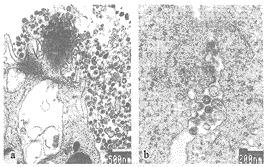

HIV-1 SH01具有HIV的典型形态特征,呈圆形或椭圆形,核心颗粒为锥形,根据切面的不同亦可表现为杆状或圆形。病毒颗粒直径一般在80~150nm之间,最大的达175nm,大小不一的特征明显(图1,a)。可观察到典型的HIV颗粒自胞膜芽生释放的全过程。出芽处胞膜起初呈新月形隆起,逐渐成半圆形、圆形,最后成完整的病毒颗粒而脱落,有的即将脱落的病毒颗粒仍通过纤细的桥样连接与细胞膜相连(图1,b)。刚释放到细胞外的病毒颗粒外膜有刺样突起,核心颗粒常缺如,此为未成熟的HIV颗粒。

图1 (a)HIV-1 SH01大小不一的特征明显,核心颗粒呈锥形、杆状或圆形。(b)HIV-1 SH01从胞膜出芽释放过程的各个阶段均可见到,一即将脱落的HIV颗粒仍通过纤细的桥样连接与细胞膜相连。

Figure 1 (a) HIV-1 SH01 particles varied in size with conical, tubular or circular cores. (b) The whole budding process of HIV-1 SH01 was shown and an HIV particle was still connected to cell membrane by a fine bridge-like linkage.

HIV-1 SH01分离株对MT4、MT2等T细胞来源的细胞系具有良好的敏感性,并诱导产生融合多核巨细胞[14],故为合体细胞诱导型(SI)T细胞敏感株[15,16]。其形态学特征与以往报道的完全一致,具有典型的锥形核心,并且大小不一的特征相当明显[3-5]。胞膜芽生释放的过程十分典型,从新月形隆起到最后形成完整的病毒颗粒脱落的各个阶段均能得到很好的显示。刚释放到胞外的HIV颗粒,包膜常有刺样突起,核心颗粒常缺如,或呈环状或圆饼状,为未成熟的病毒颗粒,但在蛋白酶的作用下,不久即可完成其最后的成熟过程,并形成最具特征性的锥形核心颗粒[4,5,35]。